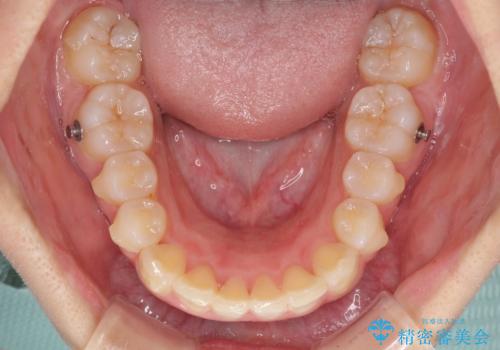

- 前歯のデコボコ気になるとのことで来院された患者様です。

上下顎ともに歯列全体の後方移動とIPR(歯と歯の間を削る)によってデコボコが解消するように設計し、インビザラインにより治療を行うこととしました。

上顎左右前歯に矮小歯があるため、上顎の奥歯は下顎に対して相対的に前方に位置することになりました。